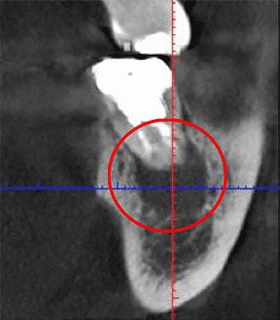

実際に「根管」の画像をご覧頂きましょう。歯の中にある黒い筋が根管です。